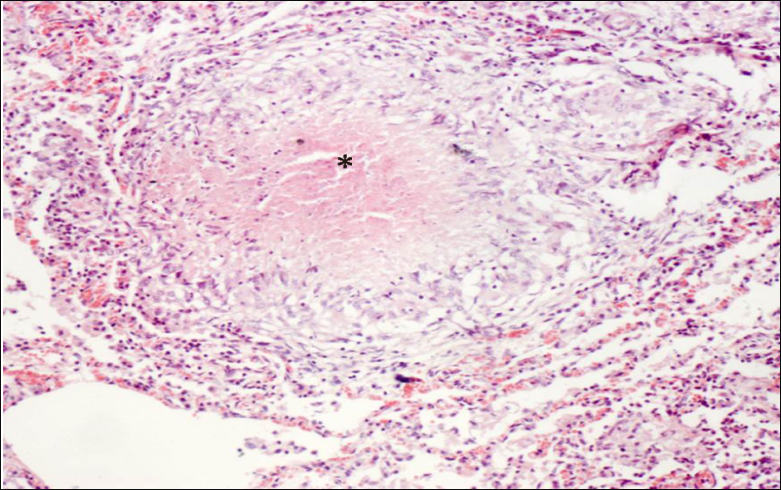

当细菌量少,毒力较低或人体免疫反应较强时,则发生以增生为主的变化,形成具有诊断价值的结核结节,结核结节(tubercle)是在细胞免疫的基础上形成的,由上皮样细胞(epithelioid cell),朗汉斯(Langhans)巨细胞加上外周局部集聚的淋巴细胞和少量反应性增生的纤维母细胞构成:

干酪样坏死典型者结节中央有干酪样坏死(*)

上皮样细胞吞噬有结核杆菌的巨噬细胞体积增大逐渐转变为上皮样细胞,呈梭形或多角形,胞浆丰富,染淡伊红色,境界不清。核呈圆或卵圆形,染色质甚少,甚至可呈空泡状,核内可有1-2个核仁。

朗格汉斯巨细胞多数上皮样细胞互相融合或一个细胞核分裂胞浆不分裂乃形成朗格汉斯巨细胞。朗格汉斯巨细胞为一种多核巨细胞,直径可达300mm,胞浆丰富。其胞浆突起常和上皮样细胞的胞质突起相连接,核与上皮样细胞核相似。核的数目由十几个到几十个不等,有超过百个者。核排列在胞浆周围呈花环状、马蹄形或密集胞体一端。

单个结核结节非常小,直径约0.1mm,肉眼和X线片不易看见。三、四个结节融合成较大结节时才能见到。这种融合结节境界分明,约粟粒大小,呈灰白半透明状。有干酪样坏死时略显微黄,可微隆起于器官表面。